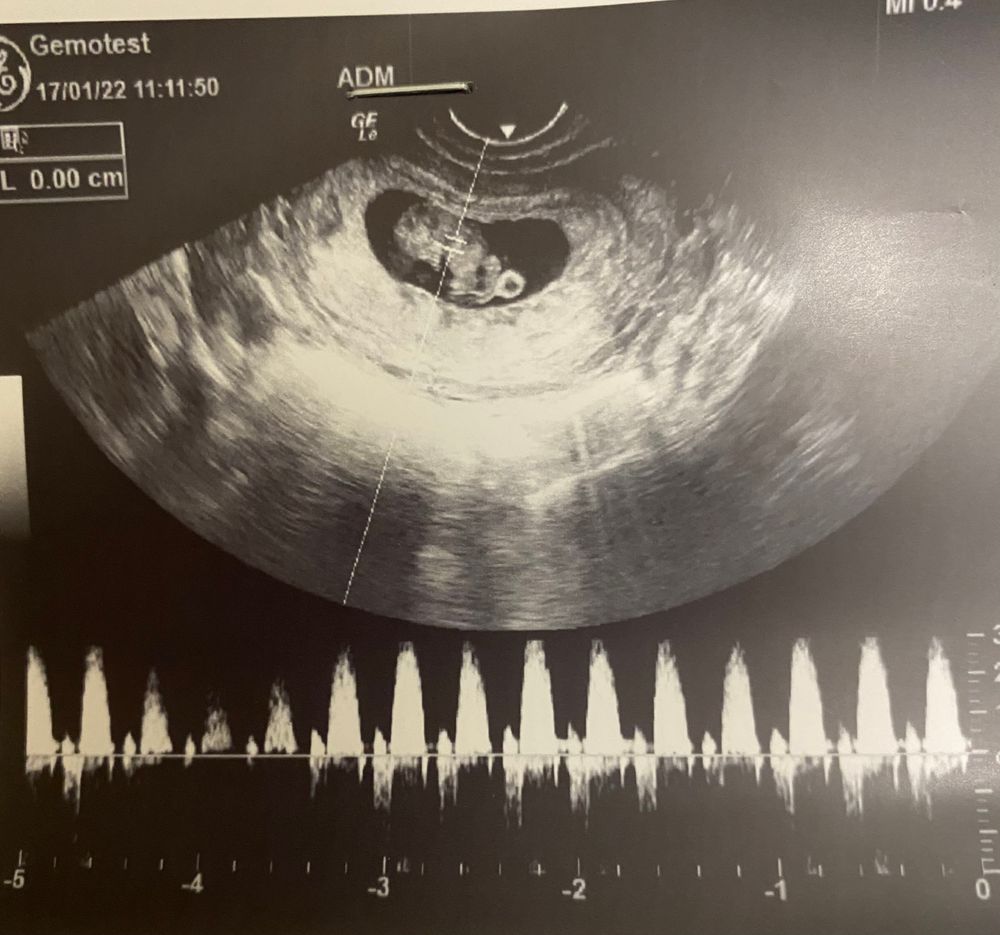

Алёна 4 года Узи 8+5 КТР 20,5 сказали срок 8 недель и 6 дней, по моим подсчётам 8+5. Сказали все хорошо, сердечко бьется, тонуса нет😊 Посмотрите еще 20 записей на эту тему Лучший ответ Sashenka Какая прелесть 😇 17.01.2022 Ответить Отменить Ответить Маргарита Поздравляю! Лёгкой беременности! 17.01.2022 Ответить Алёна Маргарита, спасибо 🙏🏻 17.01.2022 Ответить Тест 24 недели Чаты Беременных Выберите чат: Январята-2026 Февралята-2026 Мартята-2026 Апрелята-2026 Майчата-2026 Июнята-2026 Июлята-2026 Августята-2026